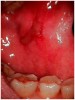

Chemotherapy employs the use of cytotoxic drugs to combat rapidly dividing cancer cells as either a primary or adjuvant modality of care. Unfortunately, most chemotherapeutic agents also affect normal rapidly dividing cells such as those of hair, bone marrow, and the lining of the gastrointestinal tract. The basement layer (stratum basale) of the oral mucosa is among those cells often affected directly by chemotherapeutic drugs. Chemotherapy also alters the vascular, inflammatory, and healing response of the oral mucosa.6 The repercussion of these changes is an ulceration that begins at the basement layer and proceeds to the surface of the mucosa causing a deep, painful sore in the mouth or oropharynx. This condition is known as mucositis (Figure 1). It is most common when the chemotherapeutic drugs are given in high doses and repeating schedules or when they are combined with radiation therapy. Clinical oral mucositis typically begins 5 to 10 days following the initiation of the regimen and lasts 7 to 14 days.7 Because the destruction of the mucosa is so deep, the ulcers can serve as conduits for infections into the bloodstream in the immunosuppressed patient. Often, mucositis can become so debilitating that it causes the patient to quit eating, which impacts systemic nutrition and compromises the patient's health. Symptoms can become so severe that it may become necessary to alter the patient's chemotherapy schedule. The severity of chemotherapy-induced mucositis is directly correlated to the degree of neutropenia, or low neutrophil count, and is most severe at the patient's nadir, the lowest point of immunosuppression.

Figure 1  Oral mucositis in a patient with graft versus host disease.